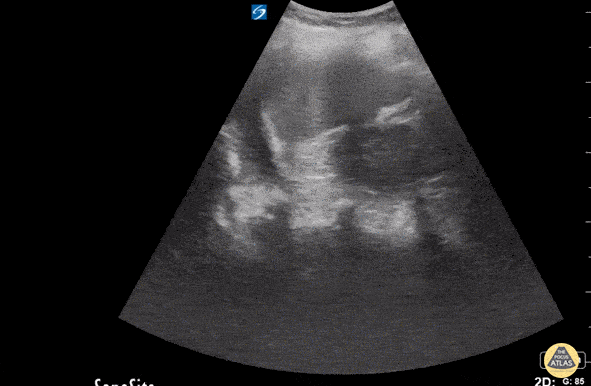

55 y/o female complains of left sided chest pain with cough, SOB, and back pain. History of falls from 8-foot ladder (8 weeks ago) and from standing (2 weeks ago). With patient in supine, US of LUQ lung in coronal view demonstrated a hypoechoic fluid collection above the left hemi-diaphragm consistent with a L pleural effusion. It is important to scan above and below the diaphragm to differentiate free fluid in thorax vs fluid in subphrenic space. US is more sensitive than plain radiographs for detecting pleural effusion and can detect smaller amounts of fluid. Crozer Chester Medical Center. Raghav Sahni, Dr. Melissa Yu, Dr. Brenton Elliot, Dr. Max Cooper.